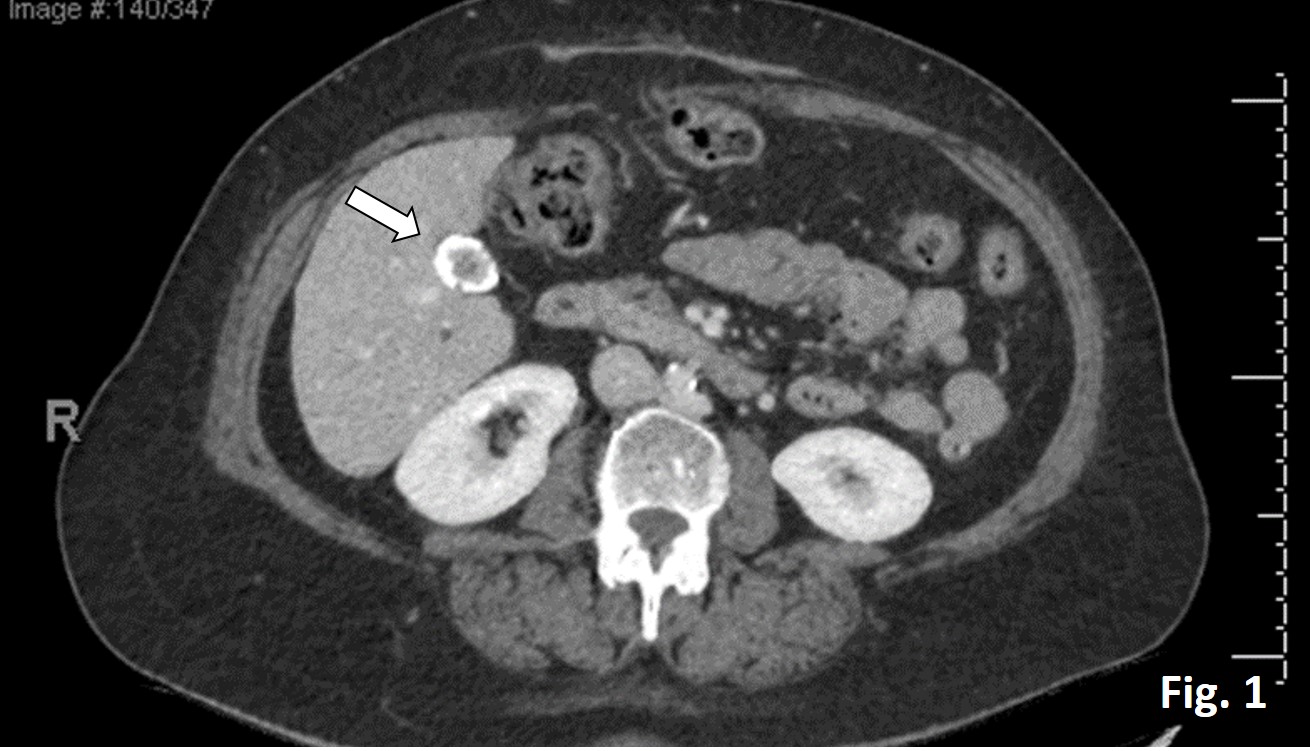

A male with an age of mid 60’s underwent cholecystectomy due to cholelithiasis. The patient’s preoperative CT scan (Fig. 1) and a microscopic image of the cholecystectomy specimen (Fig. 2) are below. What is your diagnosis and next thing to do?

It is a rare case of hyalinizing cholecystitis (HC) where the gallbladder (GB) wall calcification is highlighted on the CT scan image (Fig. 1 arrow). Microscopic findings (Fig. 2) show that the gallbladder wall is replaced by dense, hyalinized tissue transmurally. No epithelial layer or Rokitansky-Aschoff sinus is noted (Fig. 2 inset: inflammatory infiltrate only). Hence the anatomical landmarks (e. g., mucosa, muscularis) of the GB are no longer discernible.